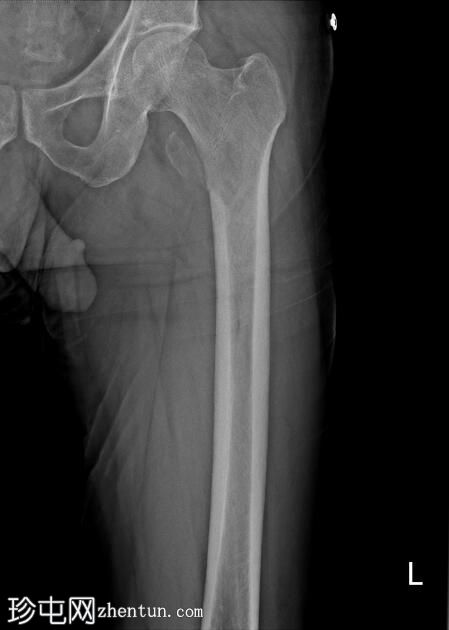

X线片

左侧股骨近端骨干可见溶骨

性病

变,延伸至股骨粗隆间区并累及小转子。

左侧小转子可见移位性

病理

性骨折。